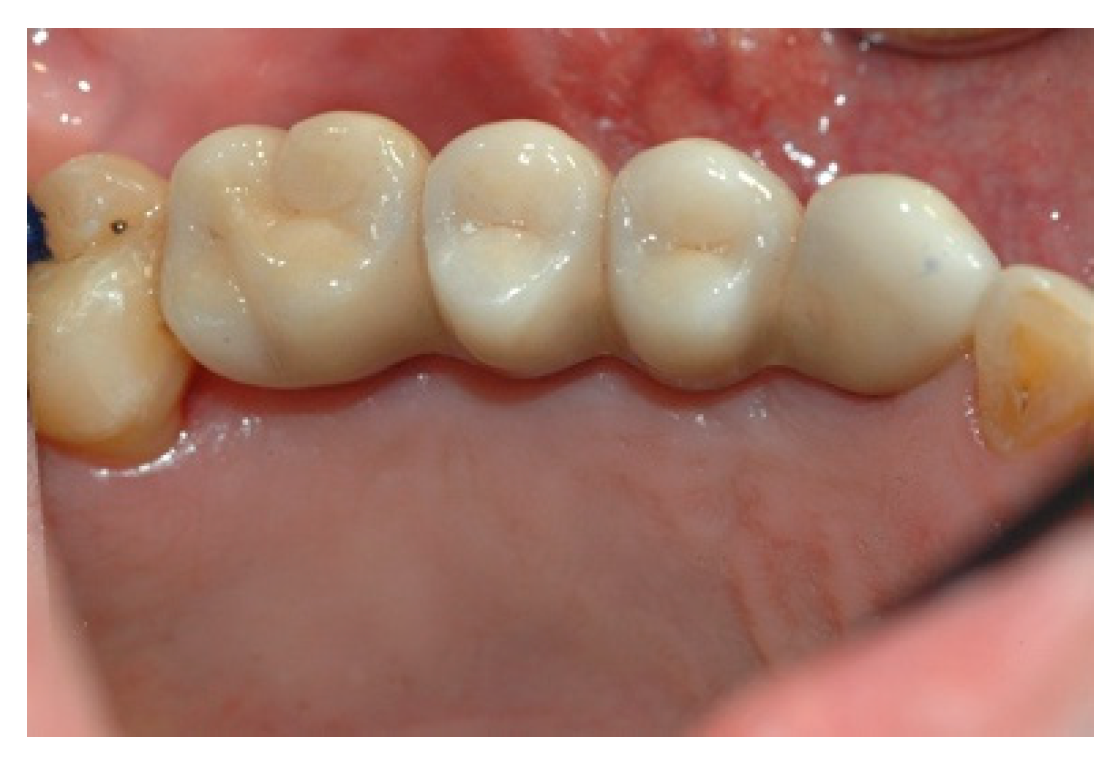

When the prosthesis was positioned, the mesostructure was fixed by tightening the screws with a torque wrench at 30 Ncm, and the superstructure was cemented by carrying out a radiographic check to evaluate the structural coherence (Figure 12, Figure 13 and Figure 14).

Figure 12. Cementing the superstructure.

Prosthesis 02 00023 g012

Figure 13. Cementing the superstructure.

Prosthesis 02 00023 g013

Figure 14. Cementing the superstructure.

Prosthesis 02 00023 g014